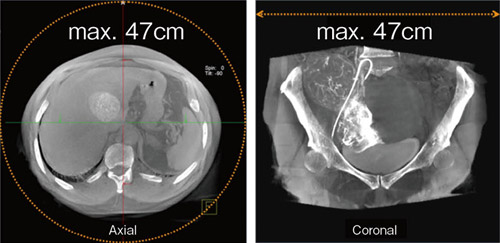

(3) Large Volume syngo DynaCT*

前述のFISによる偏心回転軌道を活用した撮影機能です。DynaCTデータ収集時の回転撮影を2回に分け,アイソセンターに対する検出器の相対位置を交互にオフセットさせることで,より広い断面の再構成を実現します(図4)。このとき,長方形の検出器を体軸に対して縦方向にセットすれば,断面積だけでなく体軸方向の撮影範囲も拡大できるため,腹部・胸部を中心とした体幹部でのDynaCT撮影時に威力を発揮すると考えています。(図5) |

図5 Large Volume syngo DynaCT画像例 |